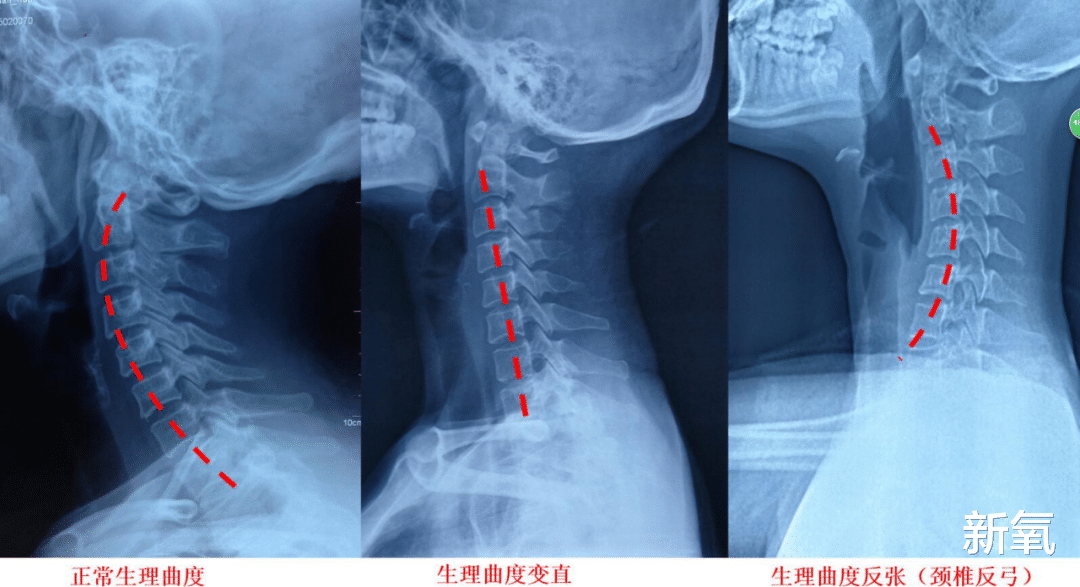

不过韩素希也有一个bug , 就是脖子前倾 , 这一点非常毁气质 , 会让整个人看起来不精神 。

看这张图 , 是不是就很明显了 , 有点背厚脖子粗的感觉 。